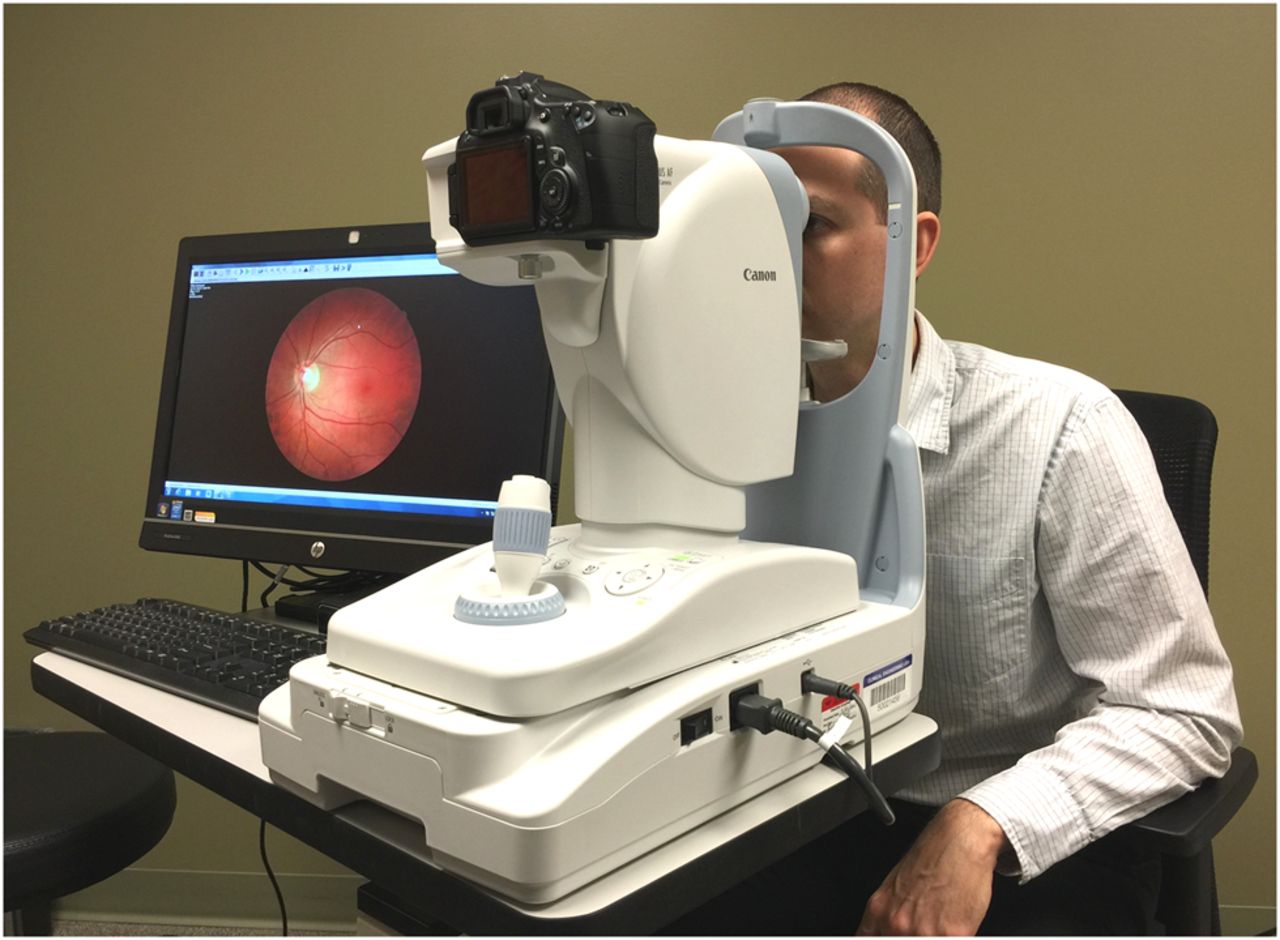

Fundus Photography

Images of the retina are taken to study the progression of retinal diseases like diabetic retinopathy, hereditary fundus dystrophies and macular degeneration.